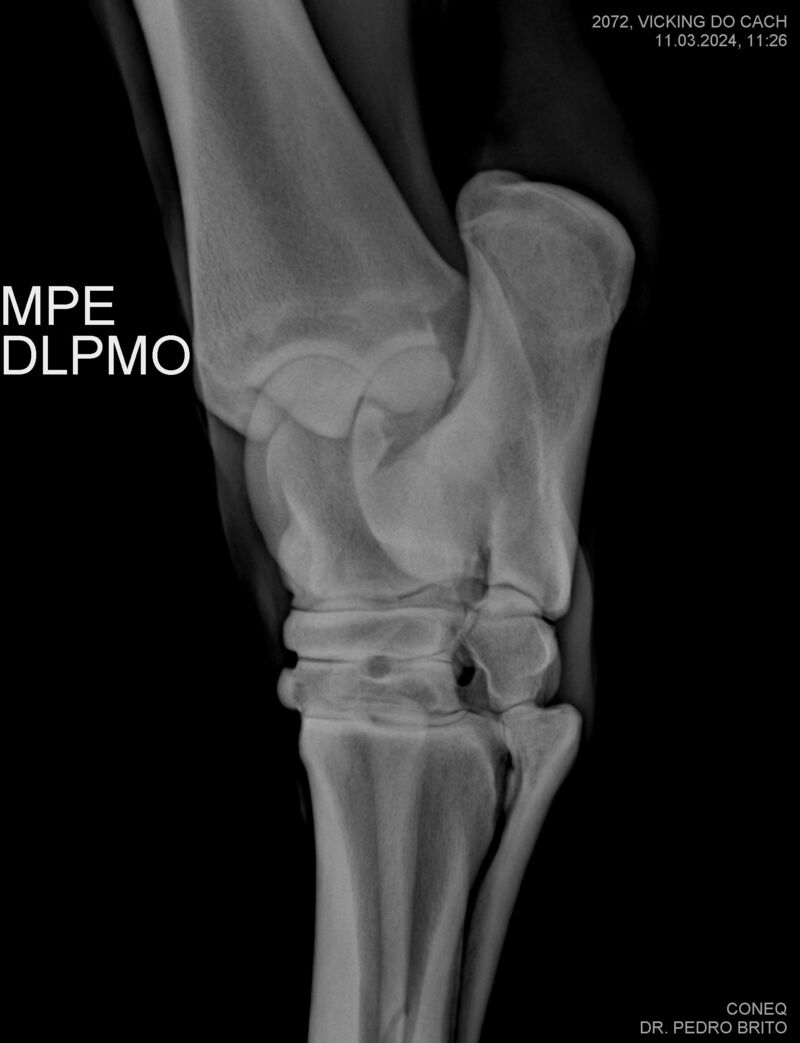

VIKING DO CACH